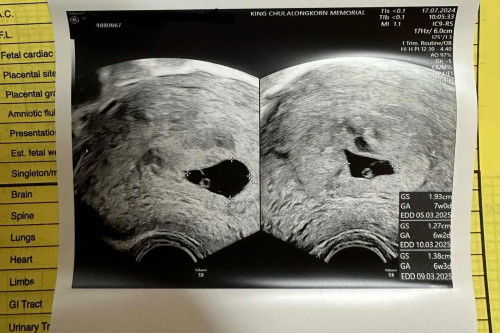

เรายังมีความหวังจะเจอน้องอยู่มั้ยคะ

8wแล้วนะยังไม่เจอน้องเลย ประจำเดือนล่าสุดวันที่19พ.ค เราใช้ที่ตรวจเจอว่าเราท้องตอน15มิถุนา แล้วฝากครรภ์วันที่19มิถุนาอัลตร้าซาวครั้งแรกเจอถุงการตั้งครรภ์ หมอนัดอัลตร้าซาวครั้งที่2วันที่3ก.ค ยังไม่เจอหัวใจน้อง วันนี้นัดครั้งที่3อัลตร้าซาวเจอแบบนี้ หมอบอกว่ากว่า90%ที่เค้าจะไม่อยู่กับเรา เราเลยรออีก2w เผื่อจะเจอน้อง เรายังมีหวังอยู่มั้ยคะ